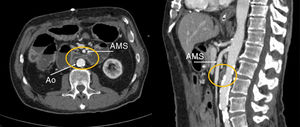

A men of 66 years old, with hypertension and diabetes, a sigmoiidectomy due to a colon cancer and after that a low anterior resection for a tumor recurrence. He is admitted in Emergency for vomiting and abdominal distension. The X-ray shows small bowel dilatation so it is decided to proceed with a CT scan. It shows a complete duodenal obstruction due to exterior compression of the third part of the duodenum by the superior mesenteric artery. The conservant treatment with nasogastric tube decompression succeed after 5 days in the hospital. He was discharged with no evidence of any other complication (Fig. 1).

Diagnosis: Superior mesenteric artery syndrome or Wilkie's syndrome.